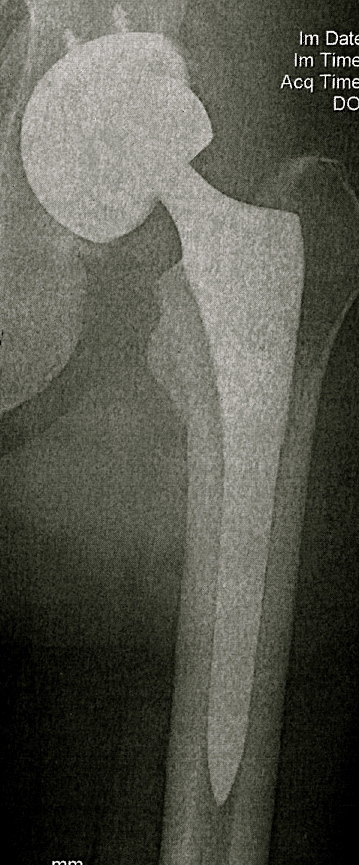

Three weeks ago, I went under the knife for my fourth hip replacement surgery in five years. Arthritis was the cause for the first two total hip replacements, faulty equipment was the cause for the subsequent “revision” hip surgeries. Seems that the parts they put in me tend to flake off titanium bits into soft tissue, blood and such. I’ve got very high levels of cobalt chromium in my blood. Heavy metal is fine for listening to, not so much to have coursing through your body. Now it’s up to my kidneys to purify my body to its former temple-like self.